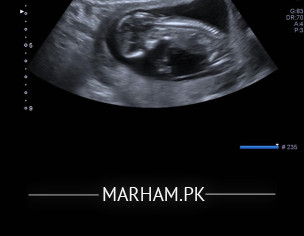

Plese tell me if you can guess the gender

Attach Photo here: